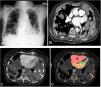

A 79-year-old woman with anaplastic carcinoma of the thyroid gland presented with hemoptysis for one week. X-ray and contrast-enhanced computed tomography (CT) of the thorax revealed multiple, well-circumscribed, rounded masses in all segments of both lungs, known as cannonball metastases (Fig. 1A, B). Most of these metastases contained pseudoaneurysms of varying sizes associated with subsegmental pulmonary artery branches (Fig. 1C). The metastases were smaller and pseudoaneurysms were absent in the patient's CT scan 2 months earlier. Thoracic CT color fusion images confirmed that the pseudoaneurysms were located in the pulmonary artery branches (Fig. 1D). Maximum intensity projection image shows multiple intra-metastatic pulmonary artery pseudoaneurysms (Movie).

(A, B) Cannonball metastases in both lungs on X-ray and thorax CT. (C) Maximum intensity projection image showing the largest pseudoaneurysm (arrow) and the terminal branches of the pulmonary artery (arrowheads). (D) The color intensity of the pseudoaneurysm indicated by the arrow in the color mapping obtained by thoracic CT fusion is the same as that of the right ventricle (*).